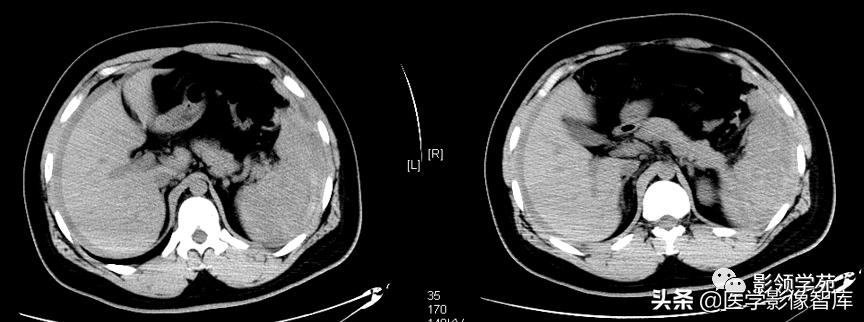

1.CT平扫:1)脾内见圆形、类圆形低密度病灶,边界较清楚。2)较大血管瘤时,脾脏体积可增大,瘤体中央可有瘢痕形成,表现为更低密度,当内部有新鲜出血时,可见高密度区。3)病灶大小不等,多为单发,也可多发,可见有斑点状、星芒状钙化灶。

2.增强扫描:1)肿瘤边缘多呈斑片状强化,静脉期和平衡期强化扩大并逐渐向中心充填,延迟后与正常脾脏密度一致。与肝血管瘤呈类似改变。2)当肿瘤中心有血栓形成或瘢痕存在时,中心可有始终不强化区域。